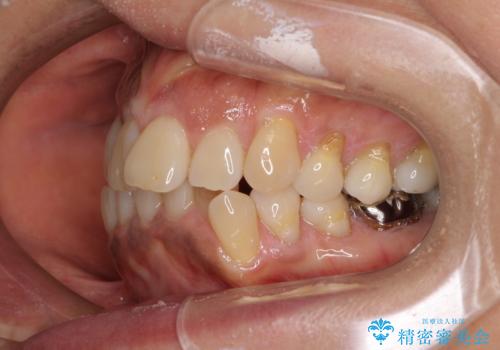

- 八重歯やクロスバイトを気にして来院された患者様です。

口元の突出感はありませんでしたが、デコボコが強く、非抜歯矯正とすると出っ歯仕上がりとなる可能性があったため、上下左右の第一小臼歯4本を抜歯し、ワイヤー装置にて矯正治療を行うこととしました。

抜歯矯正により口元が引っ込みすぎて、ほうれい線が顕著となるのではないかと心配しておりましたが、矯正後にほうれい線が気になることはなく、口元もすっきりとした感じになりました。